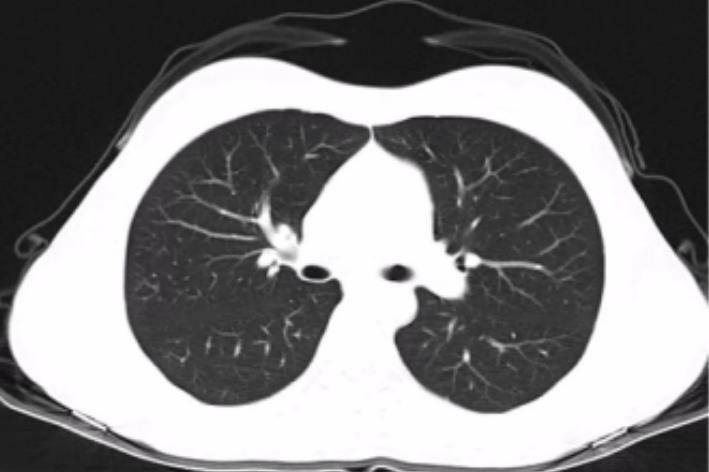

那什么是肺结节呢?

肺结节为小的局灶性、类圆形、影像学表现密度增高的阴影(直径≤3cm),可单发或多发。肺结节通常分为三种类型:

(1)纯磨玻璃结节:指在薄层CT上病变边界清楚的类圆形肺内密度增高影,但病变密度不足以掩盖其中的细小血管和细支气管影。

(2)混杂磨玻璃结节:指纯磨玻璃结节内出现明显实性成分。

(3)实性结节:指主要明显实性成分的结节。